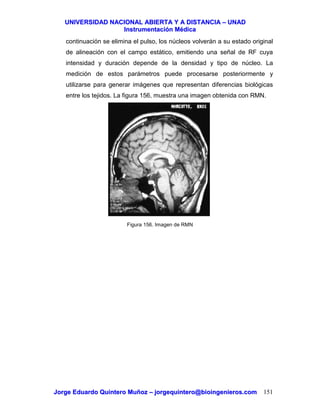

5.5 DISEÑO DE UN TERMOMETRO CLINICO

La figura 62 muestra el diagrama de bloques del módulo de temperatura de un